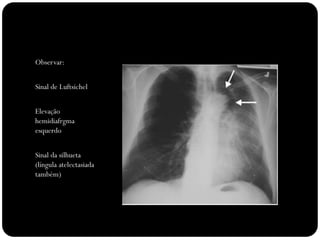

Observar:

Sinal de Luftsichel

Elevação

hemidiafrgma

esquerdo

Sinal da silhueta

(língula atelectasiada

também)